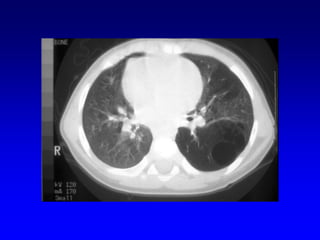

A: Xray shows bilateral bulla.

B: CT shows bilateral bulla.

C: CT after bullectomy.